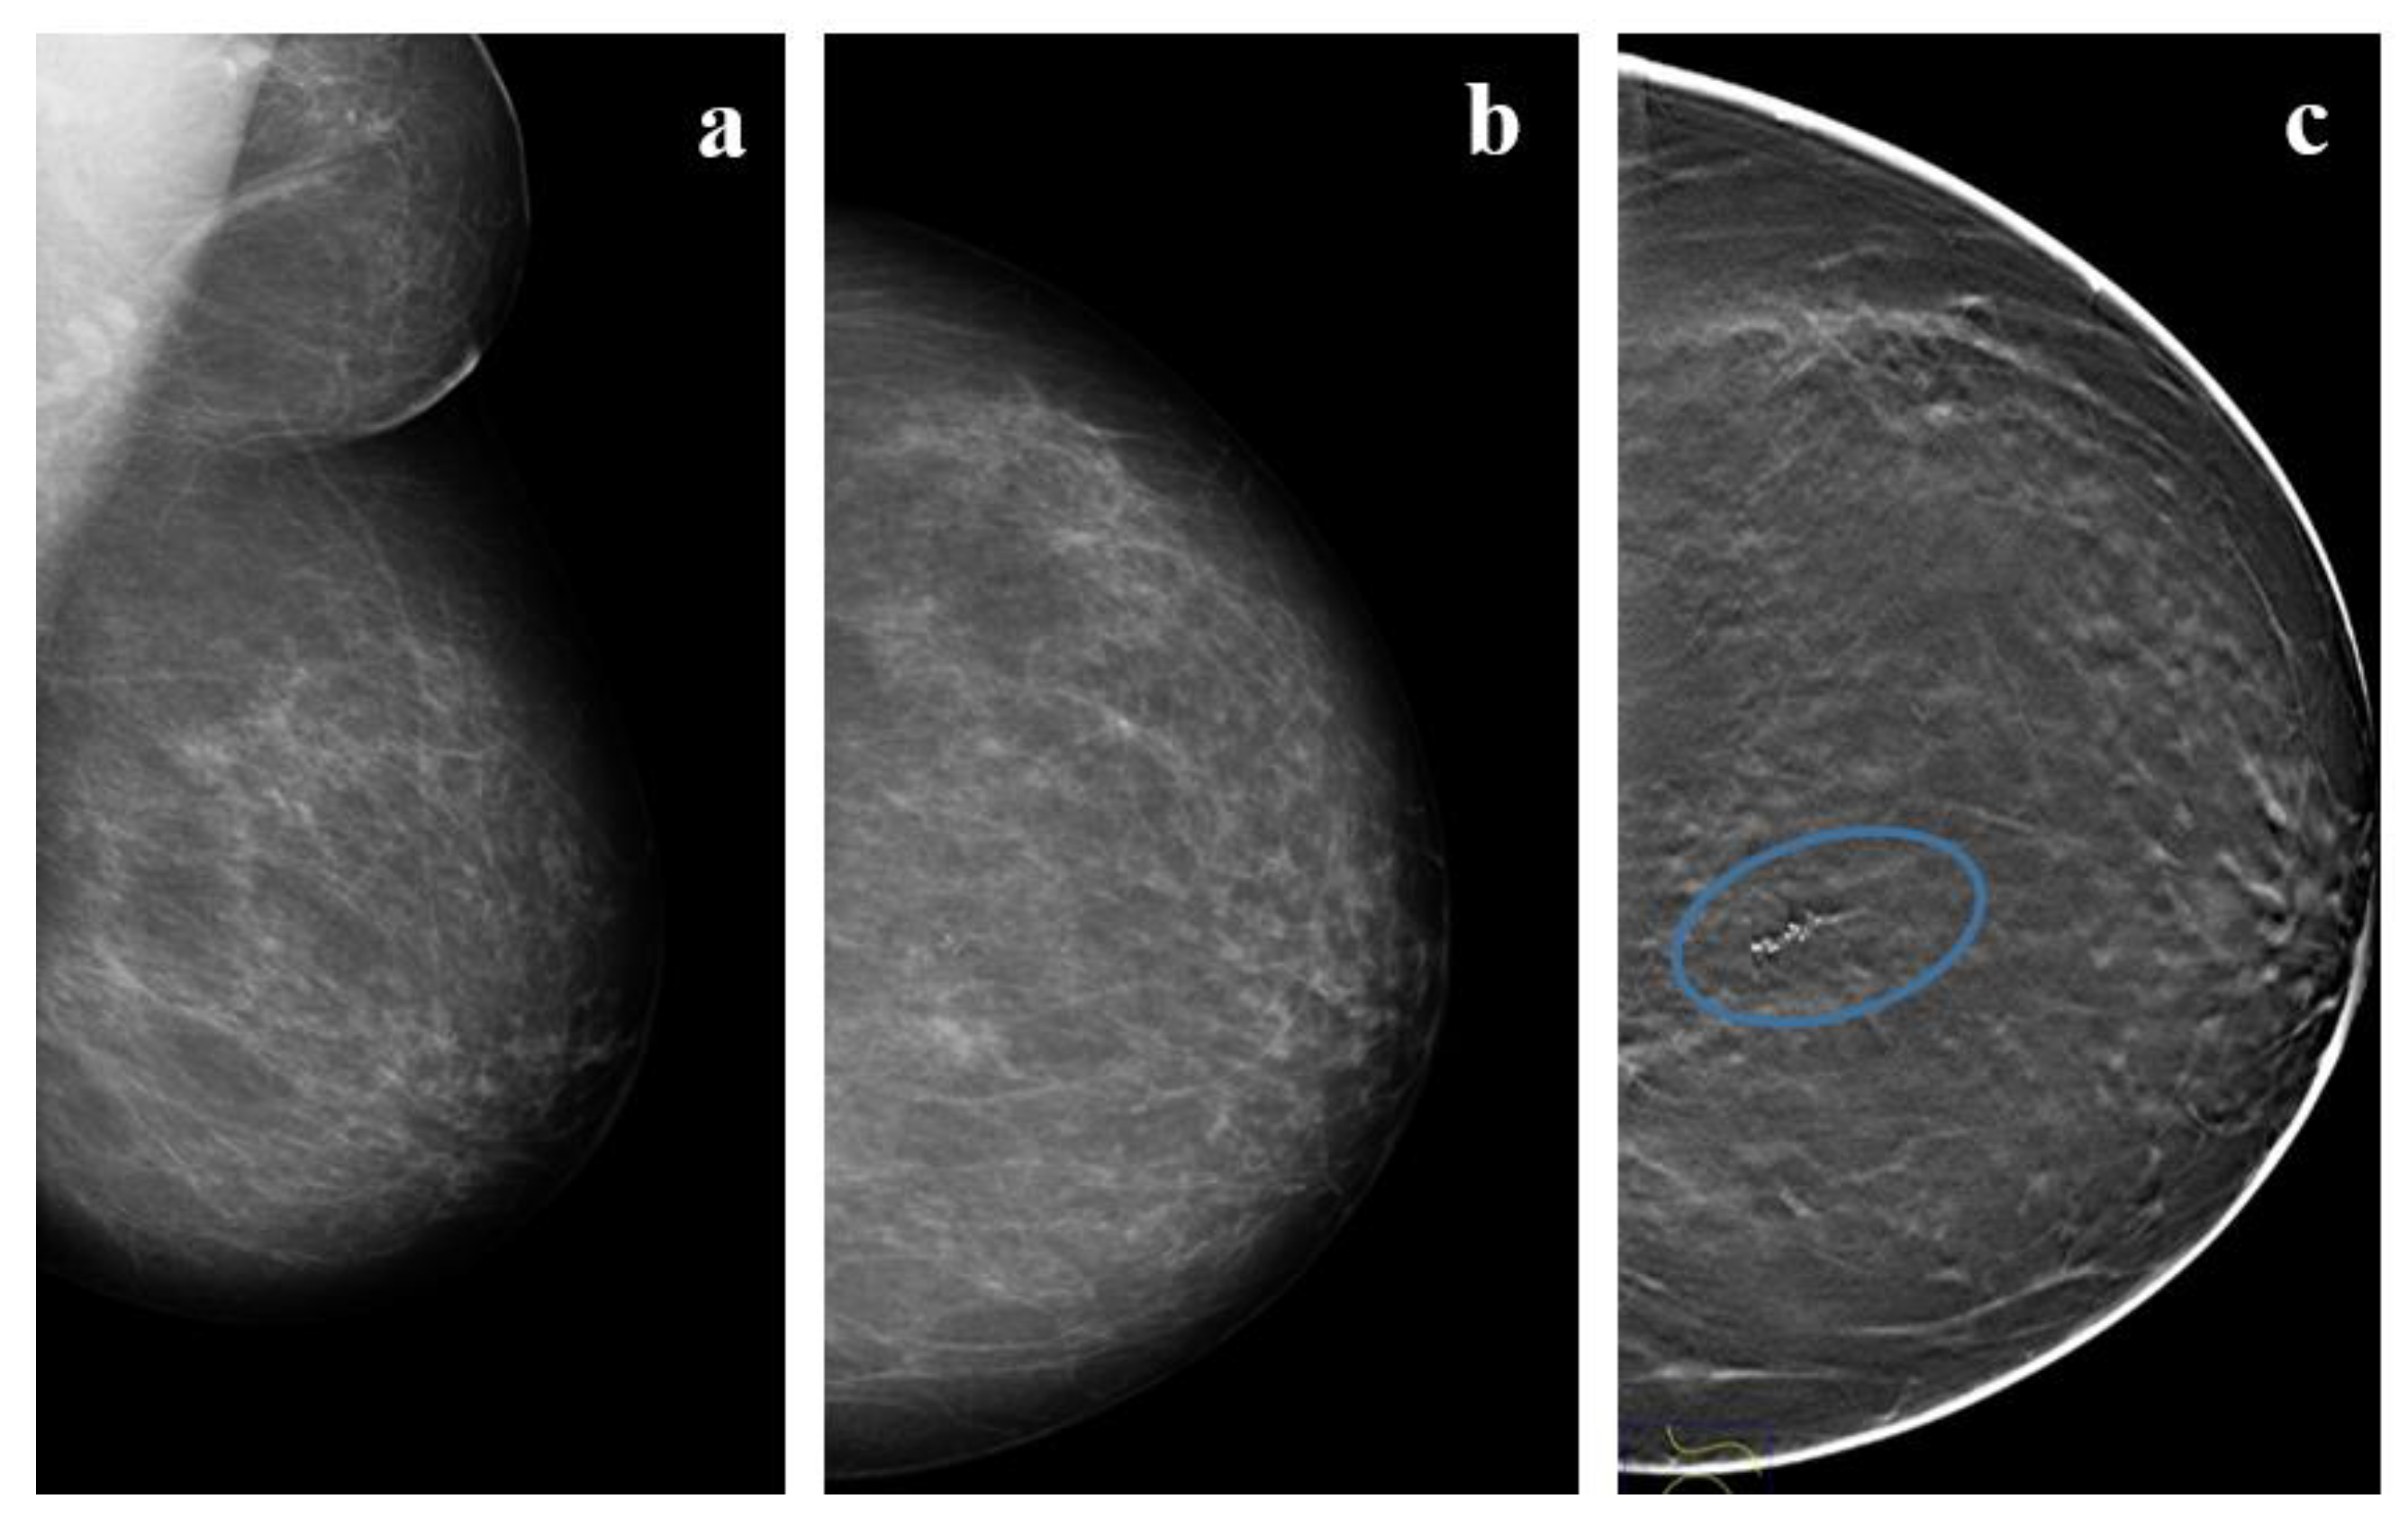

4. Radiologic Features